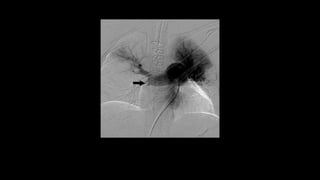

Large right upper lobe filling defect consistent with acute PE

(arrow).

Also noted are areas of decreased perfusion within the

peripheral upper and lower lobes consistent with sub segmental

emboli.